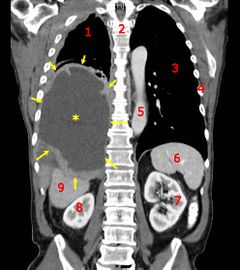

| أشعة مقطعية إكليلية تظهر سرطان كيس الرئة الخبيث. المفتاح: → ورم ←, ★ انصباب جنبي مركزي، 1&3 الرئتان، 2 العمود الفقري، 4 الضلوع، 5 الأورطى، 6 الطحال, 7&8 الكليتان، 9 الكبد.  | |